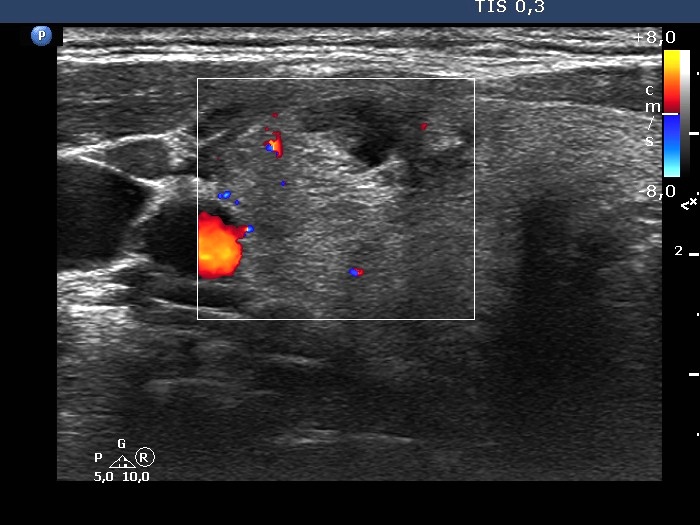

Ultrasonography. The thyroid was composed of numerous discrete lesions of various echogenicities. There was a partly cystic nodule in the upper-ventral part of the right lobe. The left lobe contained several cystic areas having comet tail artifacts.

Aspiration cytology of the largest nodule in the right lobe resulted in benign colloid goiter.